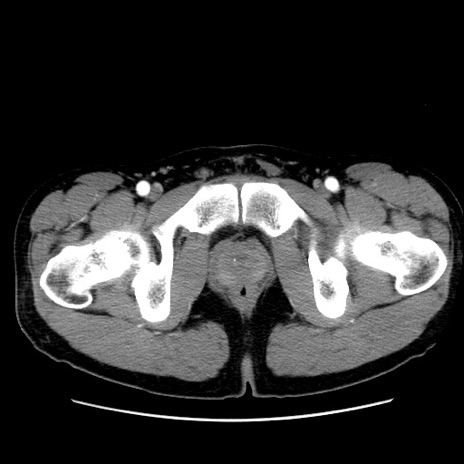

冠状断像

【症例】20歳代 男性

【主訴】心窩部痛

【現病歴】今朝より上腹部痛あり。一旦軽快していたが再度出現したため救急要請。昨日夕に白身の魚を含む刺身を食べた。

【身体所見】BP 136/89mmHg、HR 74/min、BT 37.0℃、腹部:膨満、軟、心窩部に圧痛あり。反跳痛なし、筋性防御なし、腸雑音やや亢進あり。

【データ】WBC 17700、CRP 0.48